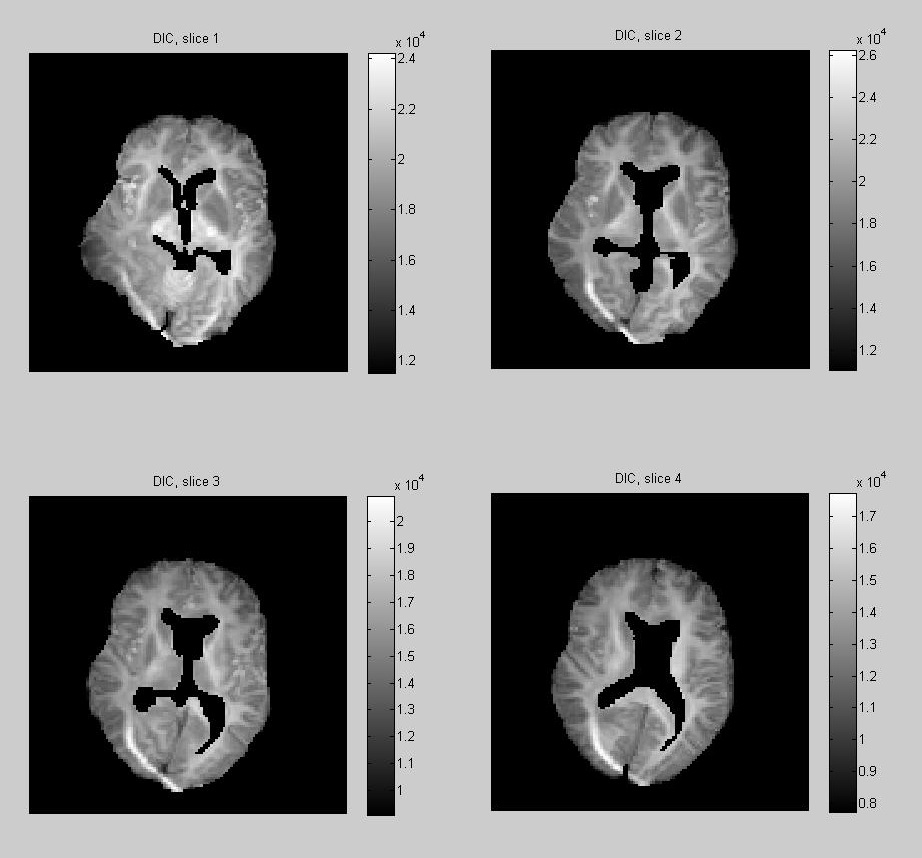

Deviance Information Criterion

The deviance information criterion (DIC), introduced by Spiegelhalter, D.J. et al. (2002), is a measure of model fitting used in Bayesian model selection as an alternative to Bayes factors. Unlike Bayes factors, DIC is well defined also when improper priors are assumed, as it is the case in our settings. It is defined as

where is the deviance, and we take conditional expectations with respect to the posterior distribution of the parameters . Defined in analogy with the toy example of Eq. (4.25), the effective number of parameters

appears as penalization term in the expression

This allows for model comparisons, lower DIC meaning a better fit to the data relatively to the effective number of parameters. In Fig. 6 the DIC is computed independently at each voxel under the 2nd and 4th-order tensor models (without regularization). Note that the voxels with the highest DIC corresponds to artefacts where the data is corrupted, and the area of high DIC correspond to complex white matter structures. We also calculated the overall DIC for all voxel under the model 2nd and 4th-order tensor models with regularization. The respective values DIC and DIC, indicate that when we penalize the model by the effective number of parameters, overall the 2th-order tensor model fits our data better than the 4th-order model. In Fig. 7 the posterior expectation of the noise parameters , are shown. When these are interpreted as residual variances in model fitting, we see that they are consistent with the DIC.